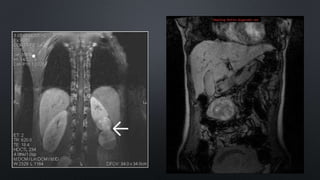

TAC: ideal para evaluar retroperitoneo

RM:

• Imágenes de gran nitidez

• Mejor definición de los grandes vasos

GABINETE (3) TAC:ideal para evaluar retroperitoneo • Identificar los distintos componentes • Diferentes coeficientes de absorción en tumor (liposarcoma) RM: • Imágenes de gran nitidez • Mejor definición de los grandes vasos Biopsia • Aguja de tipo tru cut para muestra suficiente